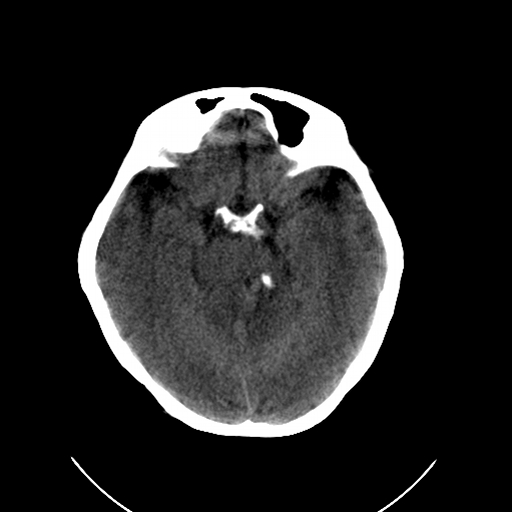

标题: CL0976:颅骨凹陷征 [打印本页]

标题: CL0976:颅骨凹陷征

女,56岁,头痛,没有其他的神经系统的阳性体征

颅底陷入是枕大孔周围骨,包括枕骨基底部、髁部和鳞部上升向颅腔内陷入的畸形。环、枢椎也随之上升、突入。多属枕骨及环枢椎先天性发育异常,也可继发于引起颅底软化的疾病、成骨不全或佝偻病等。

颅底凹陷症!这样横断位未见过,平时都是颈椎侧片所示。建议颈椎mr检查。

颅底凹陷.典型.